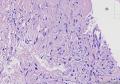

右胸壁肿物性质待查(穿刺活检),

性别

女

年龄

63

临床诊断

转移癌?淋巴瘤?

一般病史

发现肿物半年,大小2cmX2cm。患者9年前患子宫内膜癌(具体不详),化疗二周后行子宫+双附件切除。CT示:1、右前胸壁、右前上、下纵隔及右膈区多发肿物。2、肝多发病变

标本名称

右侧锁骨下方胸壁穿刺组织

大体所见

灰白灰褐色针尖尖大组织6块。